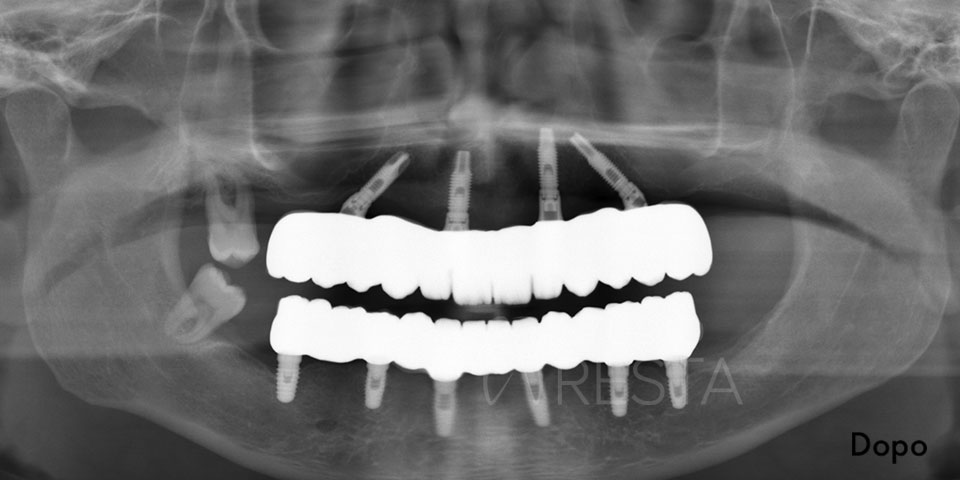

- Controllo radiografico finale: a completamento dell’intervento, eseguiamo una radiografia di controllo (OPT) per verificare l’esatto posizionamento dei quattro impianti. Spesso si noterà che i due impianti posteriori sono inclinati verso la parte posteriore dell’arcata (tilted implants), confermando il caratteristico assetto “a V rovesciata” dell’All on 4.

All on Four Senza Gengiva Finta

L’implantologia All on Four senza gengiva finta è un’opzione protesica che non prevede l’utilizzo sulle protesi dentali di gengiva artificiale. Questo approccio consente un’estetica migliore e soprattutto un aspetto più naturale delle protesi in modo da renderle perfettamente mimetizzabili.